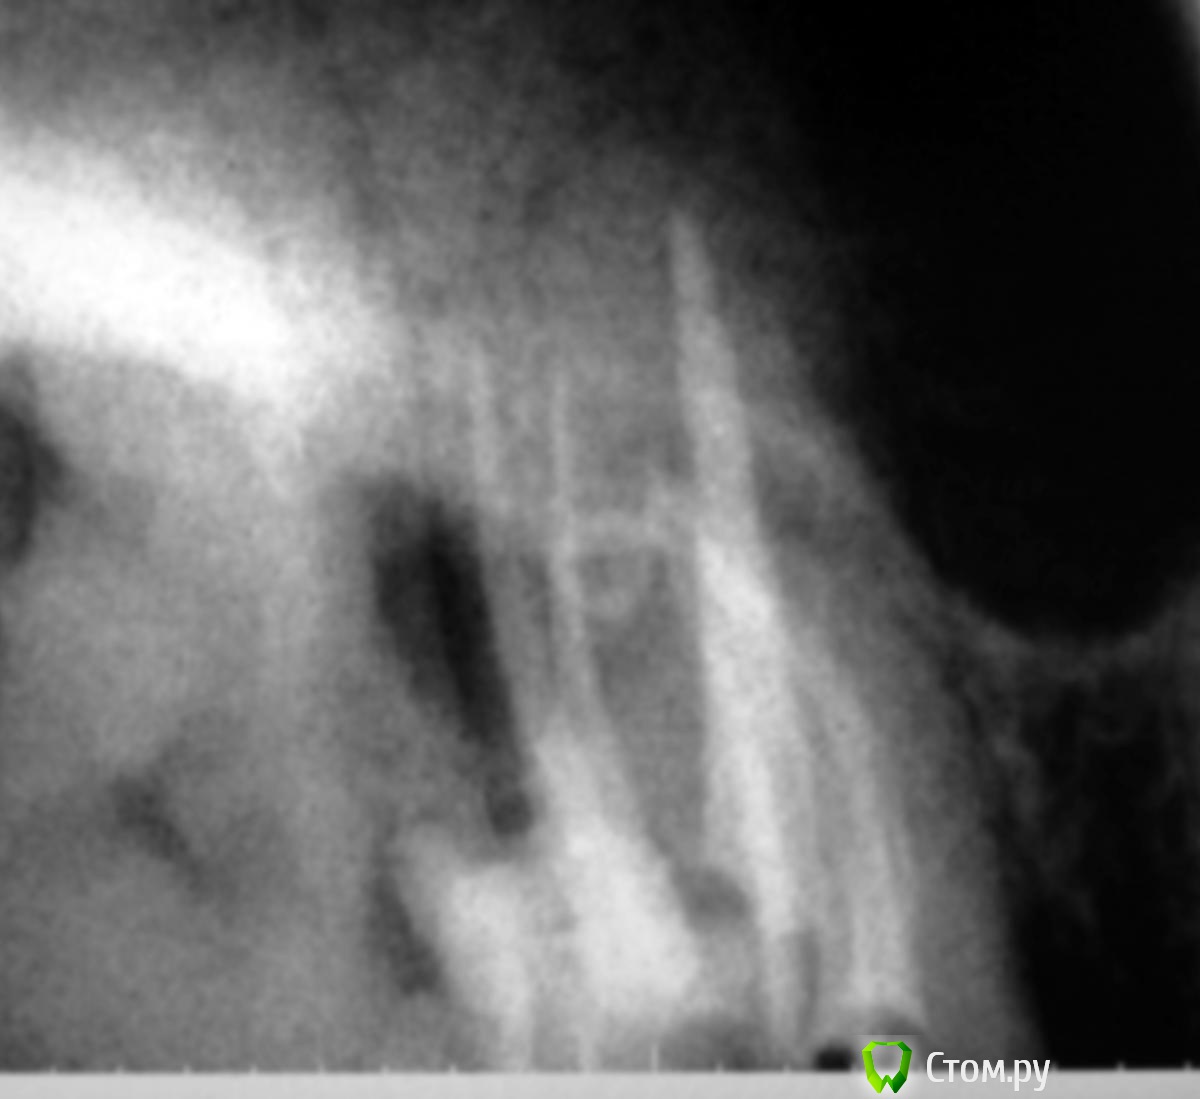

Slaggy Опубликовано 6 ноября, 2014 Автор Поделиться Опубликовано 6 ноября, 2014 Кейс некрасивый. Но какой уж есть.За качество снимков дико извиняюь. Мой рекордсмен: Пациент обратился по гарантии в клинику. 16ый зуб. Жалобы периодонтитные.снимок 2 месяца назад - Пломба поразила своей оригинальностью ((( - не суть.нашел каналы - временная пломба - Запломбировал - Шесть каналов - 3 в МВ системе, 2 в DB и небный. Вернул нашлепку на место. Обычно отправляю к доктору - виновнику торжества на пломбировку, но тут решил, что через недельку обточу и коронку, потому что МОД полость, глубоко, пломба - на снимке во всей красе. Если полностью убрать и переделать - все одно под коронку.Снимки без коффера, сделаны после снятия оптрадама. 4 Ссылка на комментарий

Dr.Sham Опубликовано 19 октября, 2014 Поделиться Опубликовано 19 октября, 2014 VRF в будущем при таком перерасширении. Щечный медиальный корень верхнего шестого - это маленький премоляр (по Славичеку), с которого начинается ведение до клыка. Поэтому прогноз плохой. Ссылка на комментарий